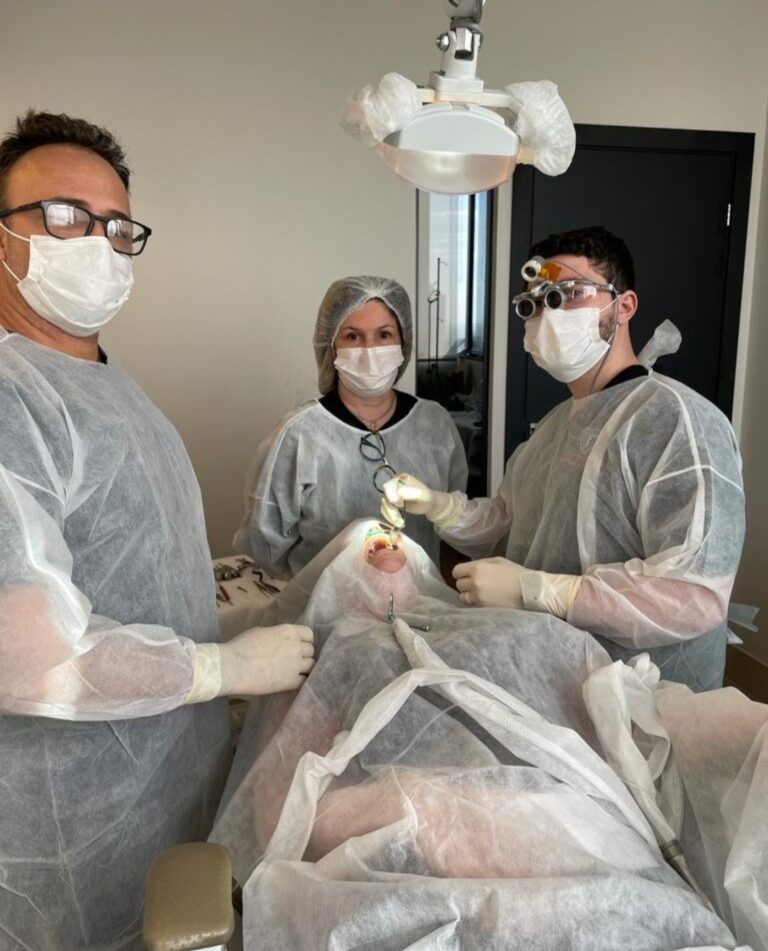

IL CORSO DI IMPLANTOLOGIA E CHIRURGIA ORALE PRATICO SU PAZIENTE IN BRASILE

ONE TO ONE

Scopri l’eccezionale opportunità formativa offerta da Cursos Internacionais de Cirurgia, il percorso ideale per chi desidera migliorare ed eccellere nella chirurgia orale e maxillo facciale

SII TU IL PRIMO OPERATORE, SEMPRE! DALL’INIZIO ALLA FINE. IL TUO ASSISTENTE SARA’ UN TUTOR DEDICATO CHE TI SEGUIRA E GUIDERA’ PASSO DOPO PASSO NELLA RISOLUZIONE DEL CASO CHIRURGICO!